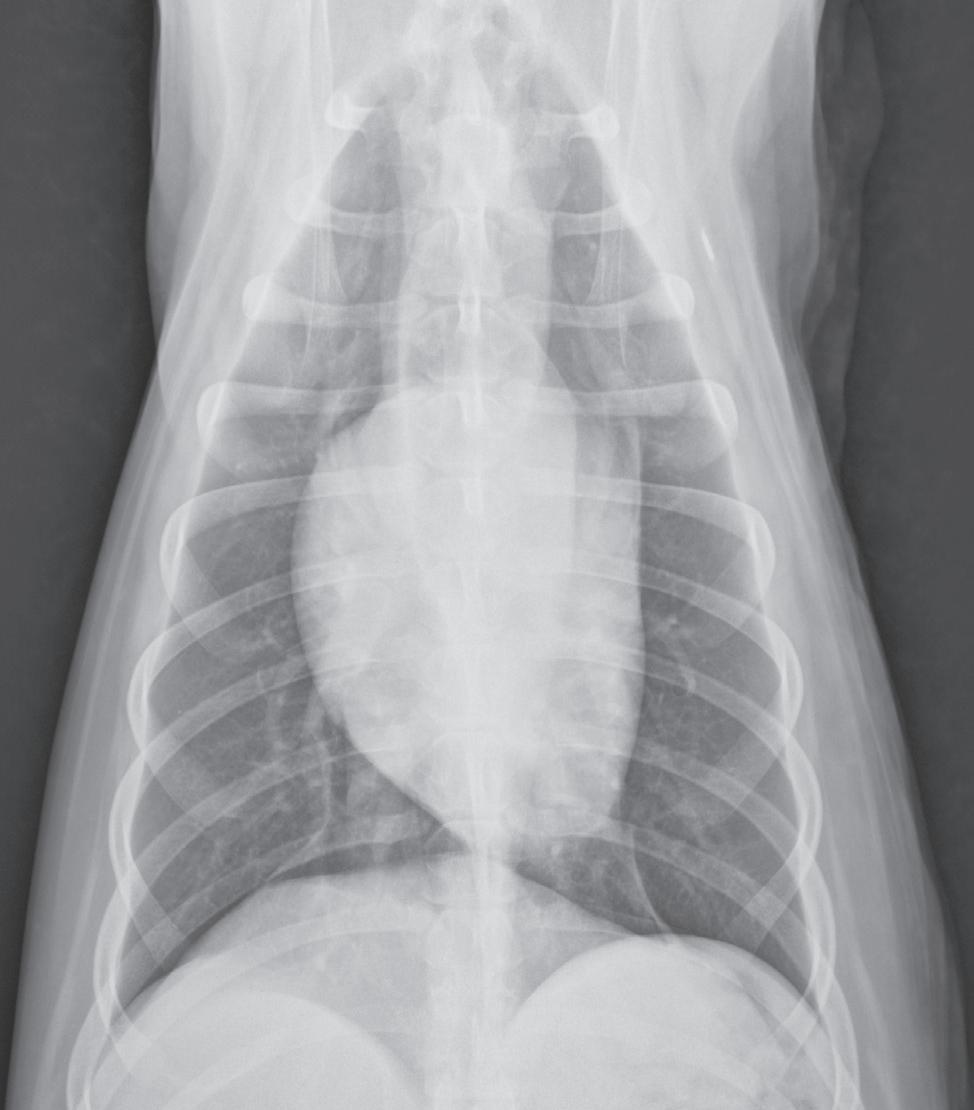

Correct orientation of a lateral view of any body part. A lateral view of the thorax is shown here.

1-3. Correct orientation of a ventrodorsal view of the head, spine, thorax, abdomen, or pelvis. A ventrodorsal view of the thorax is shown here. This same orientation would be used if the image were a dorsoventral view.